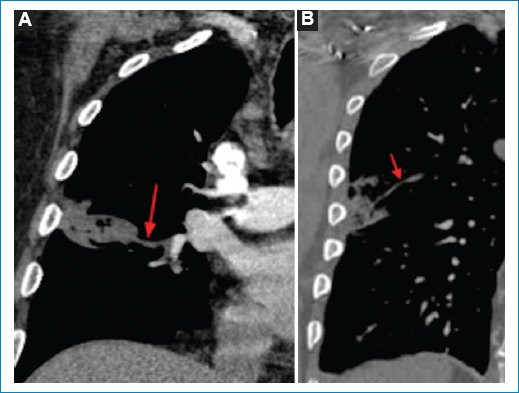

- Opacidad periférica con radiolucencia central: con una especificidad del 98% y sensibilidad del 46%, es el signo más específico para IP5. Consiste en una opacidad consolidativa periférica que contiene áreas de radiolucencia central. Dicho hallazgo se debe principalmente al llenado alveolar con contenido hemático, que se traduce en áreas de vidrio esmerilado central. También es considerada secundaria a necrosis central, con una reacción inflamatoria alrededor, opacidad consolidativa periférica, donde las zonas más excéntricas pueden representar un tejido viable (Fig. 1)6.

- Opacidad en cuña: presenta una especificidad del 60% y una sensibilidad del 52%5. Se trata de uno de los signos más característicos de IP, se describe como una opacidad de base pleural ancha y vértice dirigido hacia el hilio pulmonar de forma triangular, ubicada a lo largo de la superficie de la pleura visceral (costal, diafragmática, mediastínica o interlobular)3. La asociación de dicha opacidad con EP fue descrita por primera vez por Hampton en 1940 y es conocido como “joroba de Hamptom”, donde encontraron que dicha morfología en cuña era más probable en las consolidaciones observadas en pacientes con EP que en pacientes sin EP7. Como ya hemos mencionado, la ubicación periférica se debe a la afección de las ramas subsegmentarias de la arteria pulmonar, que además explicaría el dolor pleurítico y el frote pleural característicos de este cuadro clínico (Fig. 2).